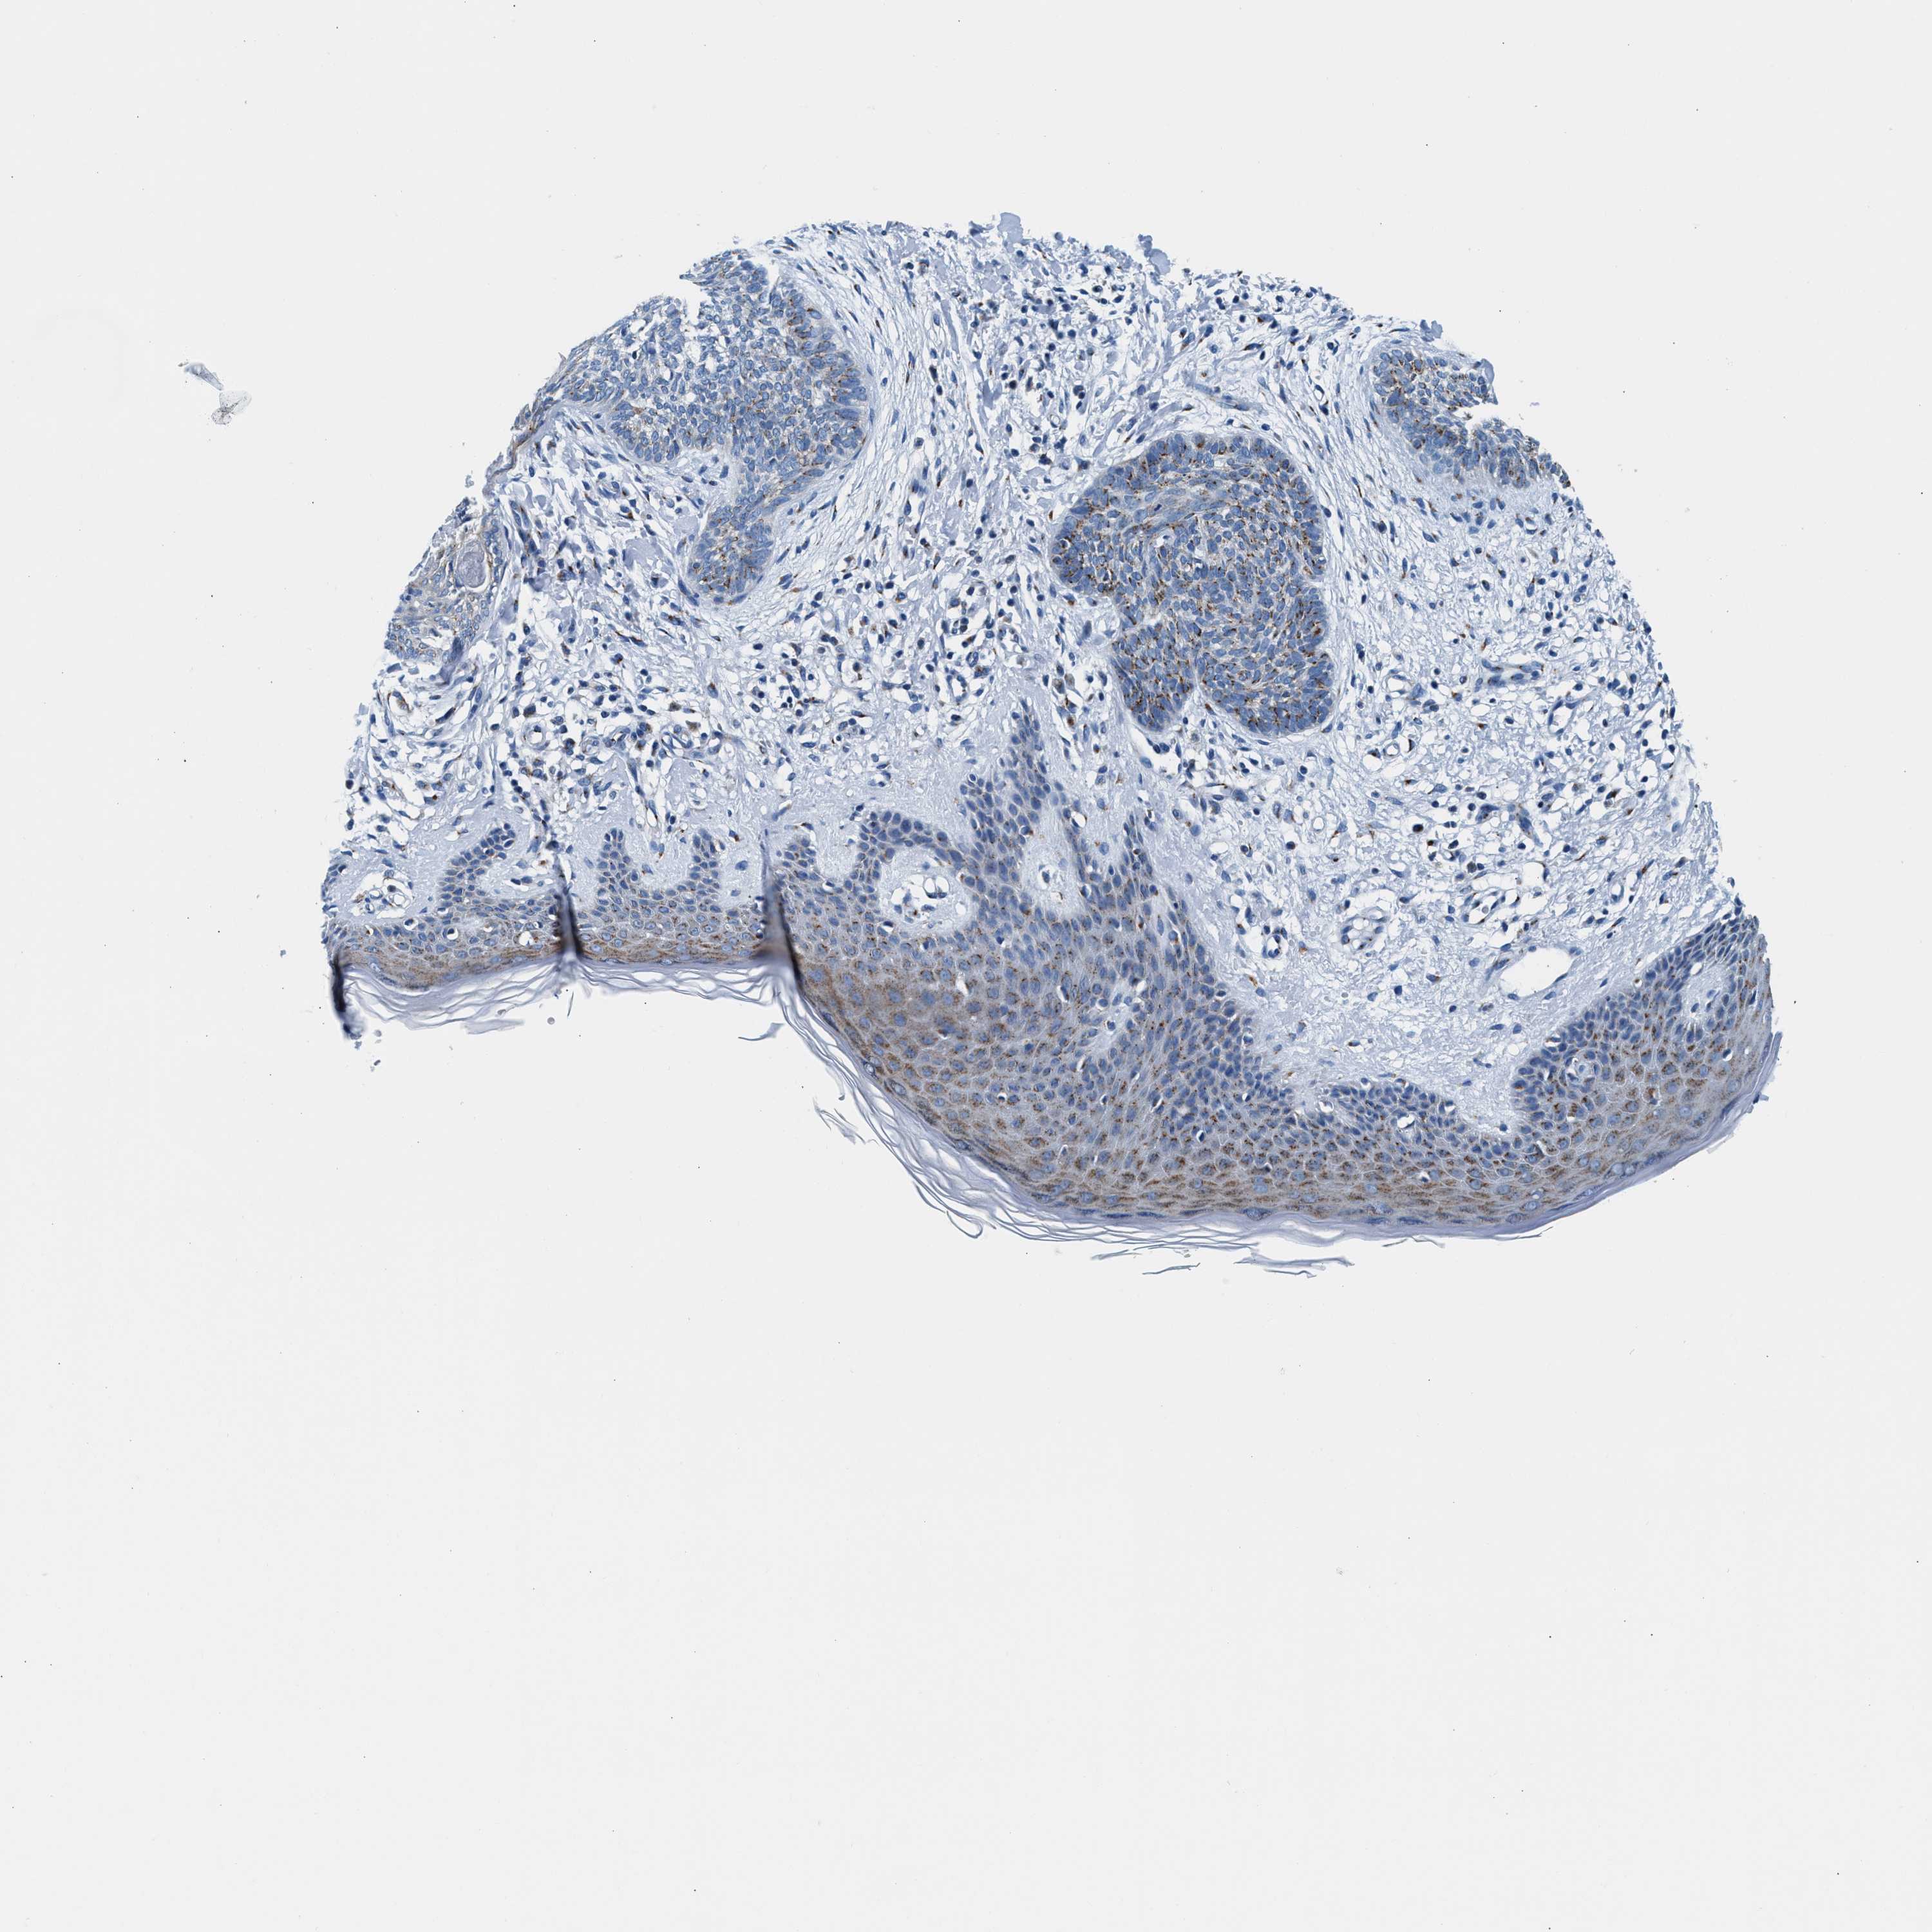

Basal cell and squamous cell cancer

SKIN CANCER - Protein expressioni

A mouse-over function shows sample information and annotation data. Click on an image to view it in a full screen mode. Samples can be filtered based on level of antibody staining by selecting one or several of the following categories: high, medium, low and not detected. The assay and annotation is described here.

Each image is clickable and will lead to virtual microscopy that enables deeper exploration of all samples and also displays staining intensity scores, fraction scores and subcellular localization as well as patient and tissue information for each sample.

Antibody HPA022988

Squamous cell carcinoma in situ, NOS

Squamous cell carcinoma, NOS

Squamous cell carcinoma, metastatic, NOS

Basal cell carcinoma

Adnexal tumor, benign